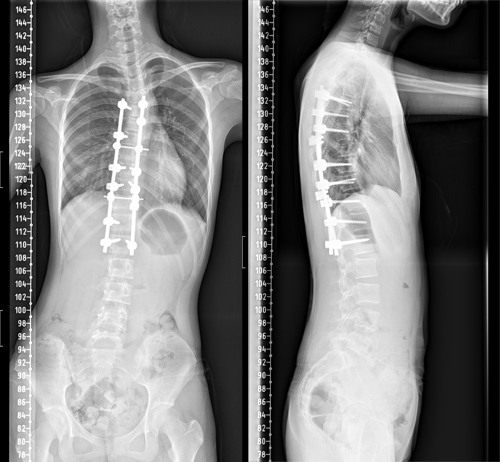

骨三科脊柱外科医护团队与麻醉科、手术室等进行了充分的术前讨论,制定周密的麻醉及手术方案。由朱述浪主任主刀,黄波副主任医师及汪智文医师共同为患者实施了后路脊柱侧弯矫形+胸廓成型手术,手术当中采用间接去旋转+多节段Ponte截骨松解技术。为了减少异体血的输入,术中采用了自体血回输,还使用了神经电生理监测为手术保驾护航,将术中置钉过程中可能损伤脊髓或神经根的风险降到最低。经过4个多小时的艰苦奋战,手术顺利完成。

术后护理团队制定了详细的护理计划,严密观察患者生命体征及切口情况。在科室全体医护人员的共同努力下,小冰术后各项指标恢复良好,术后68小时便拔除引流管,并佩戴支具下床活动。复查脊柱全长片提示脊柱S型弯曲得到了充分矫正,双肩等高,剃刀背畸形消失。术后,小冰终于可以正常平卧睡觉,而且身高达到164.5cm,较术前足足增高了4.5cm。